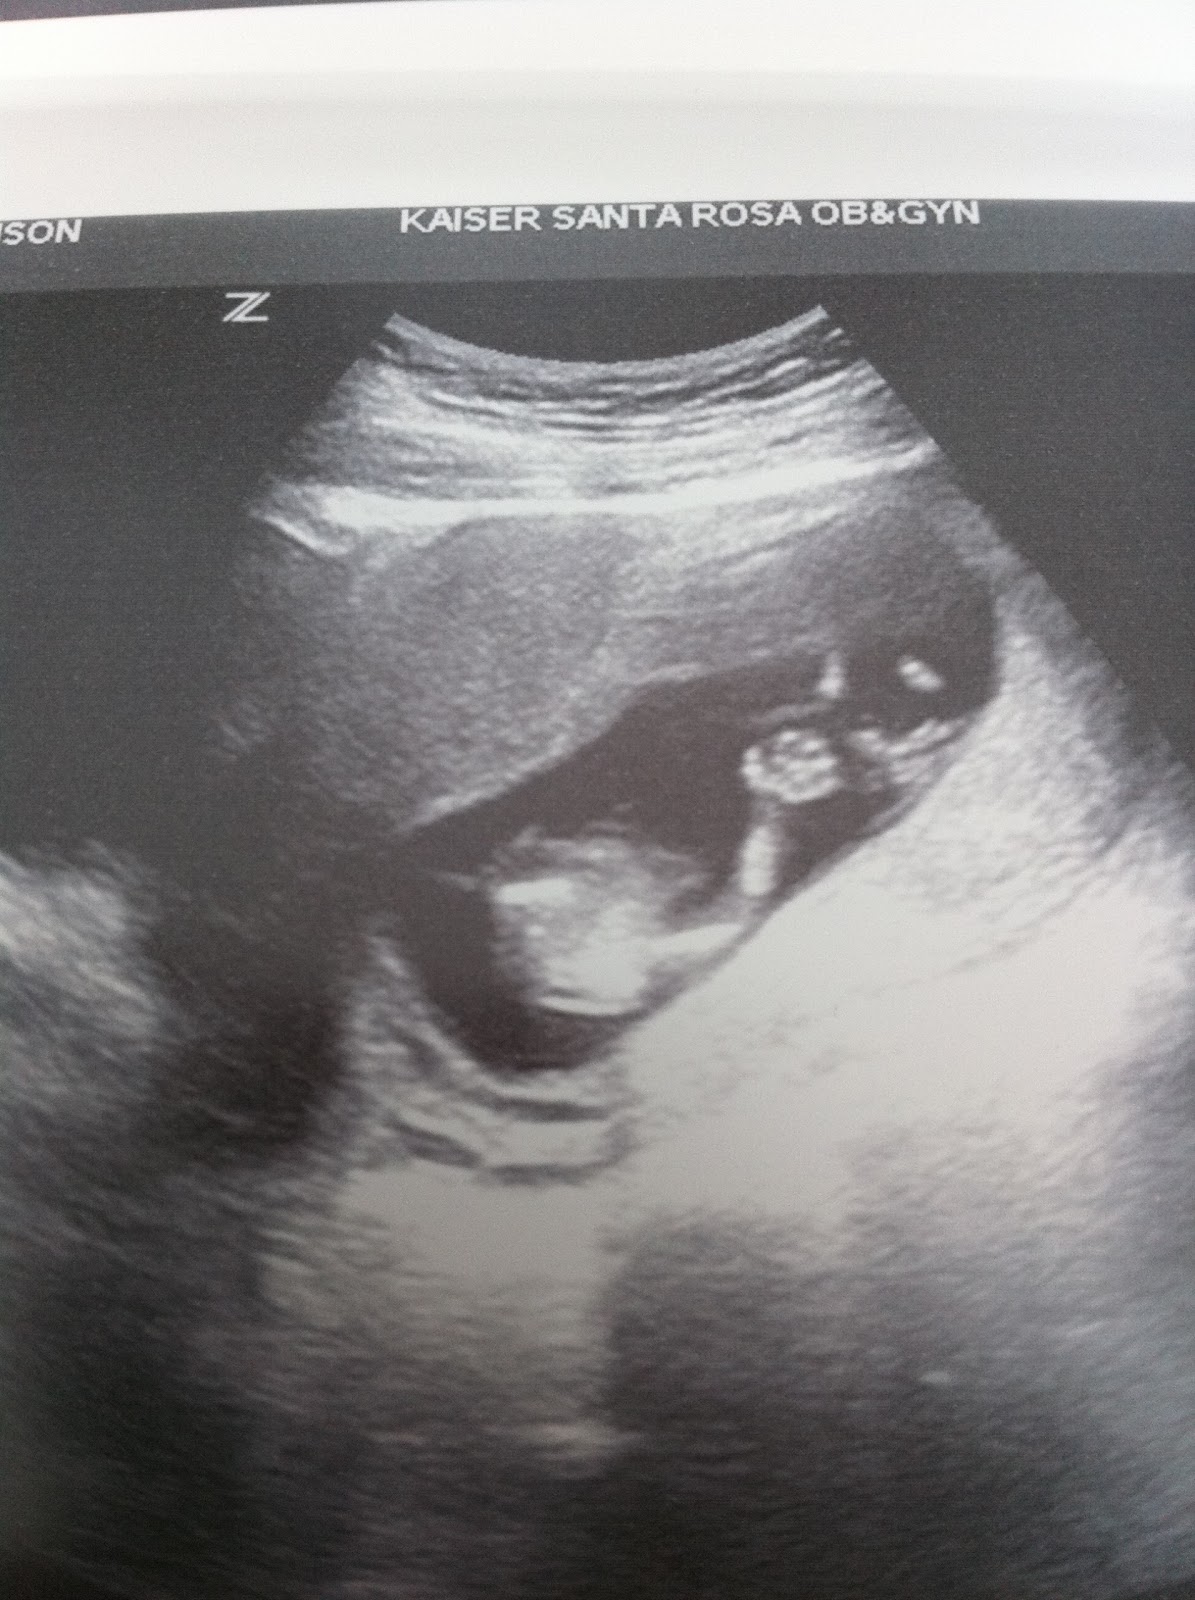

{Believe it or not we had our 3rd ultrasound in 2 weeks yesterday! The nurse we had was amazing! She did the ultrasound just for fun and so we could hear the heartbeat while Nicolai was there with me! She printed us a bunch of pictures and she got some amazing photos! This first one shows the baby's spine so clearly!}

{This one is just a really cute profile picture and you can see the amazing little feet sticking up in the air! It was kicking and moving around like crazy!}

{In this one she caught a shot of the little hand jumping around! You can see it so clearly! It was so amazing, I can't even describe it! I'm so excited!}